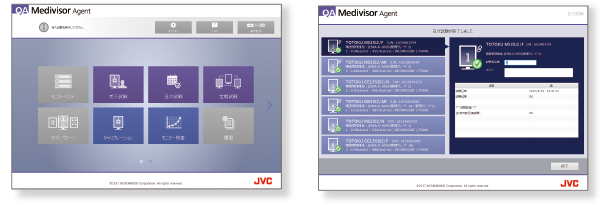

QA - Zintegrowany system kontroli jakości

Oprogramowanie QA Medivisor Agent zapewnia możliwość kalibracji i wykonania standardowych testów kontroli jakości QA*. Łatwy i intuicyjny w obsłudze interfejs ułatwia skuteczne i szybkie zarządzanie codzienną pracą w dziale radiologii.

Wraz z monitorem dostarczane jest oprogramowanie w wersji uproszczonej QA Medivisor Agent LE.

Samodzielna kalibracja

Zintegrowany czujnik przedni w monitorach serii i3 pozwala na samodzielne, zgodnie z ustawionym harmonogramem, wykonanie przez monitor okresowej kalibracji do standardu DICOM.